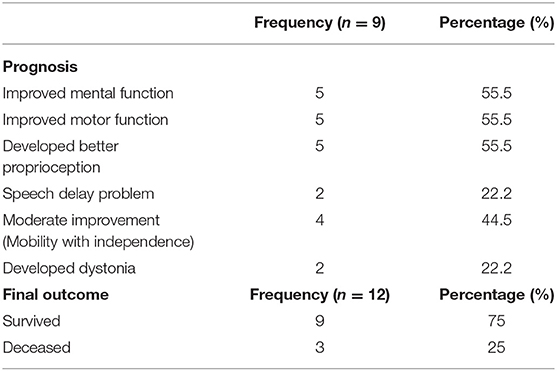

A total of 14 patients with ANEC were identified; two patients were excluded due to the inability to meet the ANEC radiological criteria. Patients' ages ranged from 10 months to 6 years (mean 30.92 months, median 22 months, standard deviation 20.63). Nine patients (75%) were female. All patients presented with preceding febrile illness in the form of upper respiratory tract infection (URTI) symptoms, or gastrointestinal symptoms in the form of vomiting or diarrhea, and altered level of consciousness. Seizures were the initial presentation in eight cases (66.7%). Brain imaging was carried out using Axial, Sagittal, and Coronal T1,T2, FLAIR, diffusion, and susceptibility weighted images which showed characteristic high signal intensity on axial T2 and FLAIR with variable degree of involvement of both thalami in all cases. Diffusion restriction was also seen, while the susceptibility sequence showed dark signal intensity with blooming, indicating hemorrhagic changes. Out of 12 patients, five (41.7%) had brainstem involvement. Follow up brain MRIs were done 2–3 months after the initial presentation, which showed signs of improvement on 33.3%, and 66.7% (n = 8) showed no signs of improvement. The clinical and radiological presentations are summarized in Tables 1, 2. Figures 1–4 show brain MRIs for selected patients.

Figure 4. Axial T2 (A–C) and FLAIR (D–F) showing swelling and abnormal high signal intensity of both thalami, basal ganglia, and cerebellum.